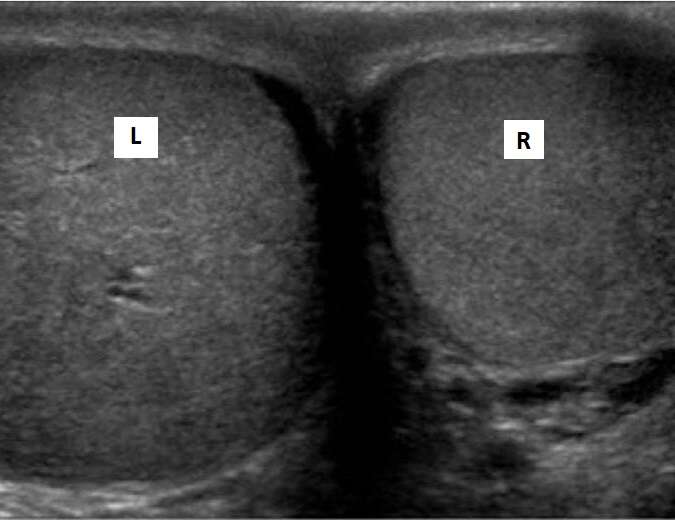

Scrotal ultrasonography is used to visualize the scrotum and other organs, such as the testicles and epididymis (tubes immediately next to the testicles that collect sperm). The scrotum, a flesh-covered pouch between the legs at the base of the penis, is where the male reproductive organs, the testicles, are located.

It helps determine the cyst/tumour in the scrotum, the size and symmetry of the testicles, the origin of pain in the testicles, and abnormal blood flow in the testicles caused by testicular torsion. It is also recommended to determine the cause of male infertility.